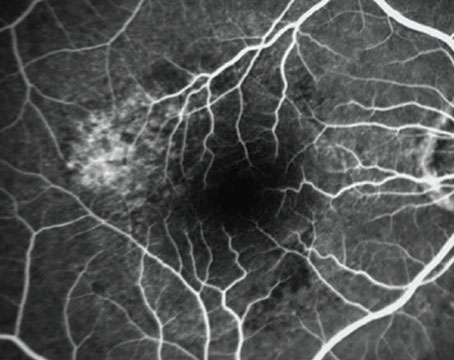

10 answers about PCV and anti-VEGF resistance

How to diagnose and manage polypoidal choroidal vasculopathy, a key subtype of choroidal neovascularization in exudative macular degeneration.

‘Twig’ occlusions among the branches

A unique finding of incidental retinal vein occlusion in a healthy patient with newly diagnosed age-related macular degeneration.